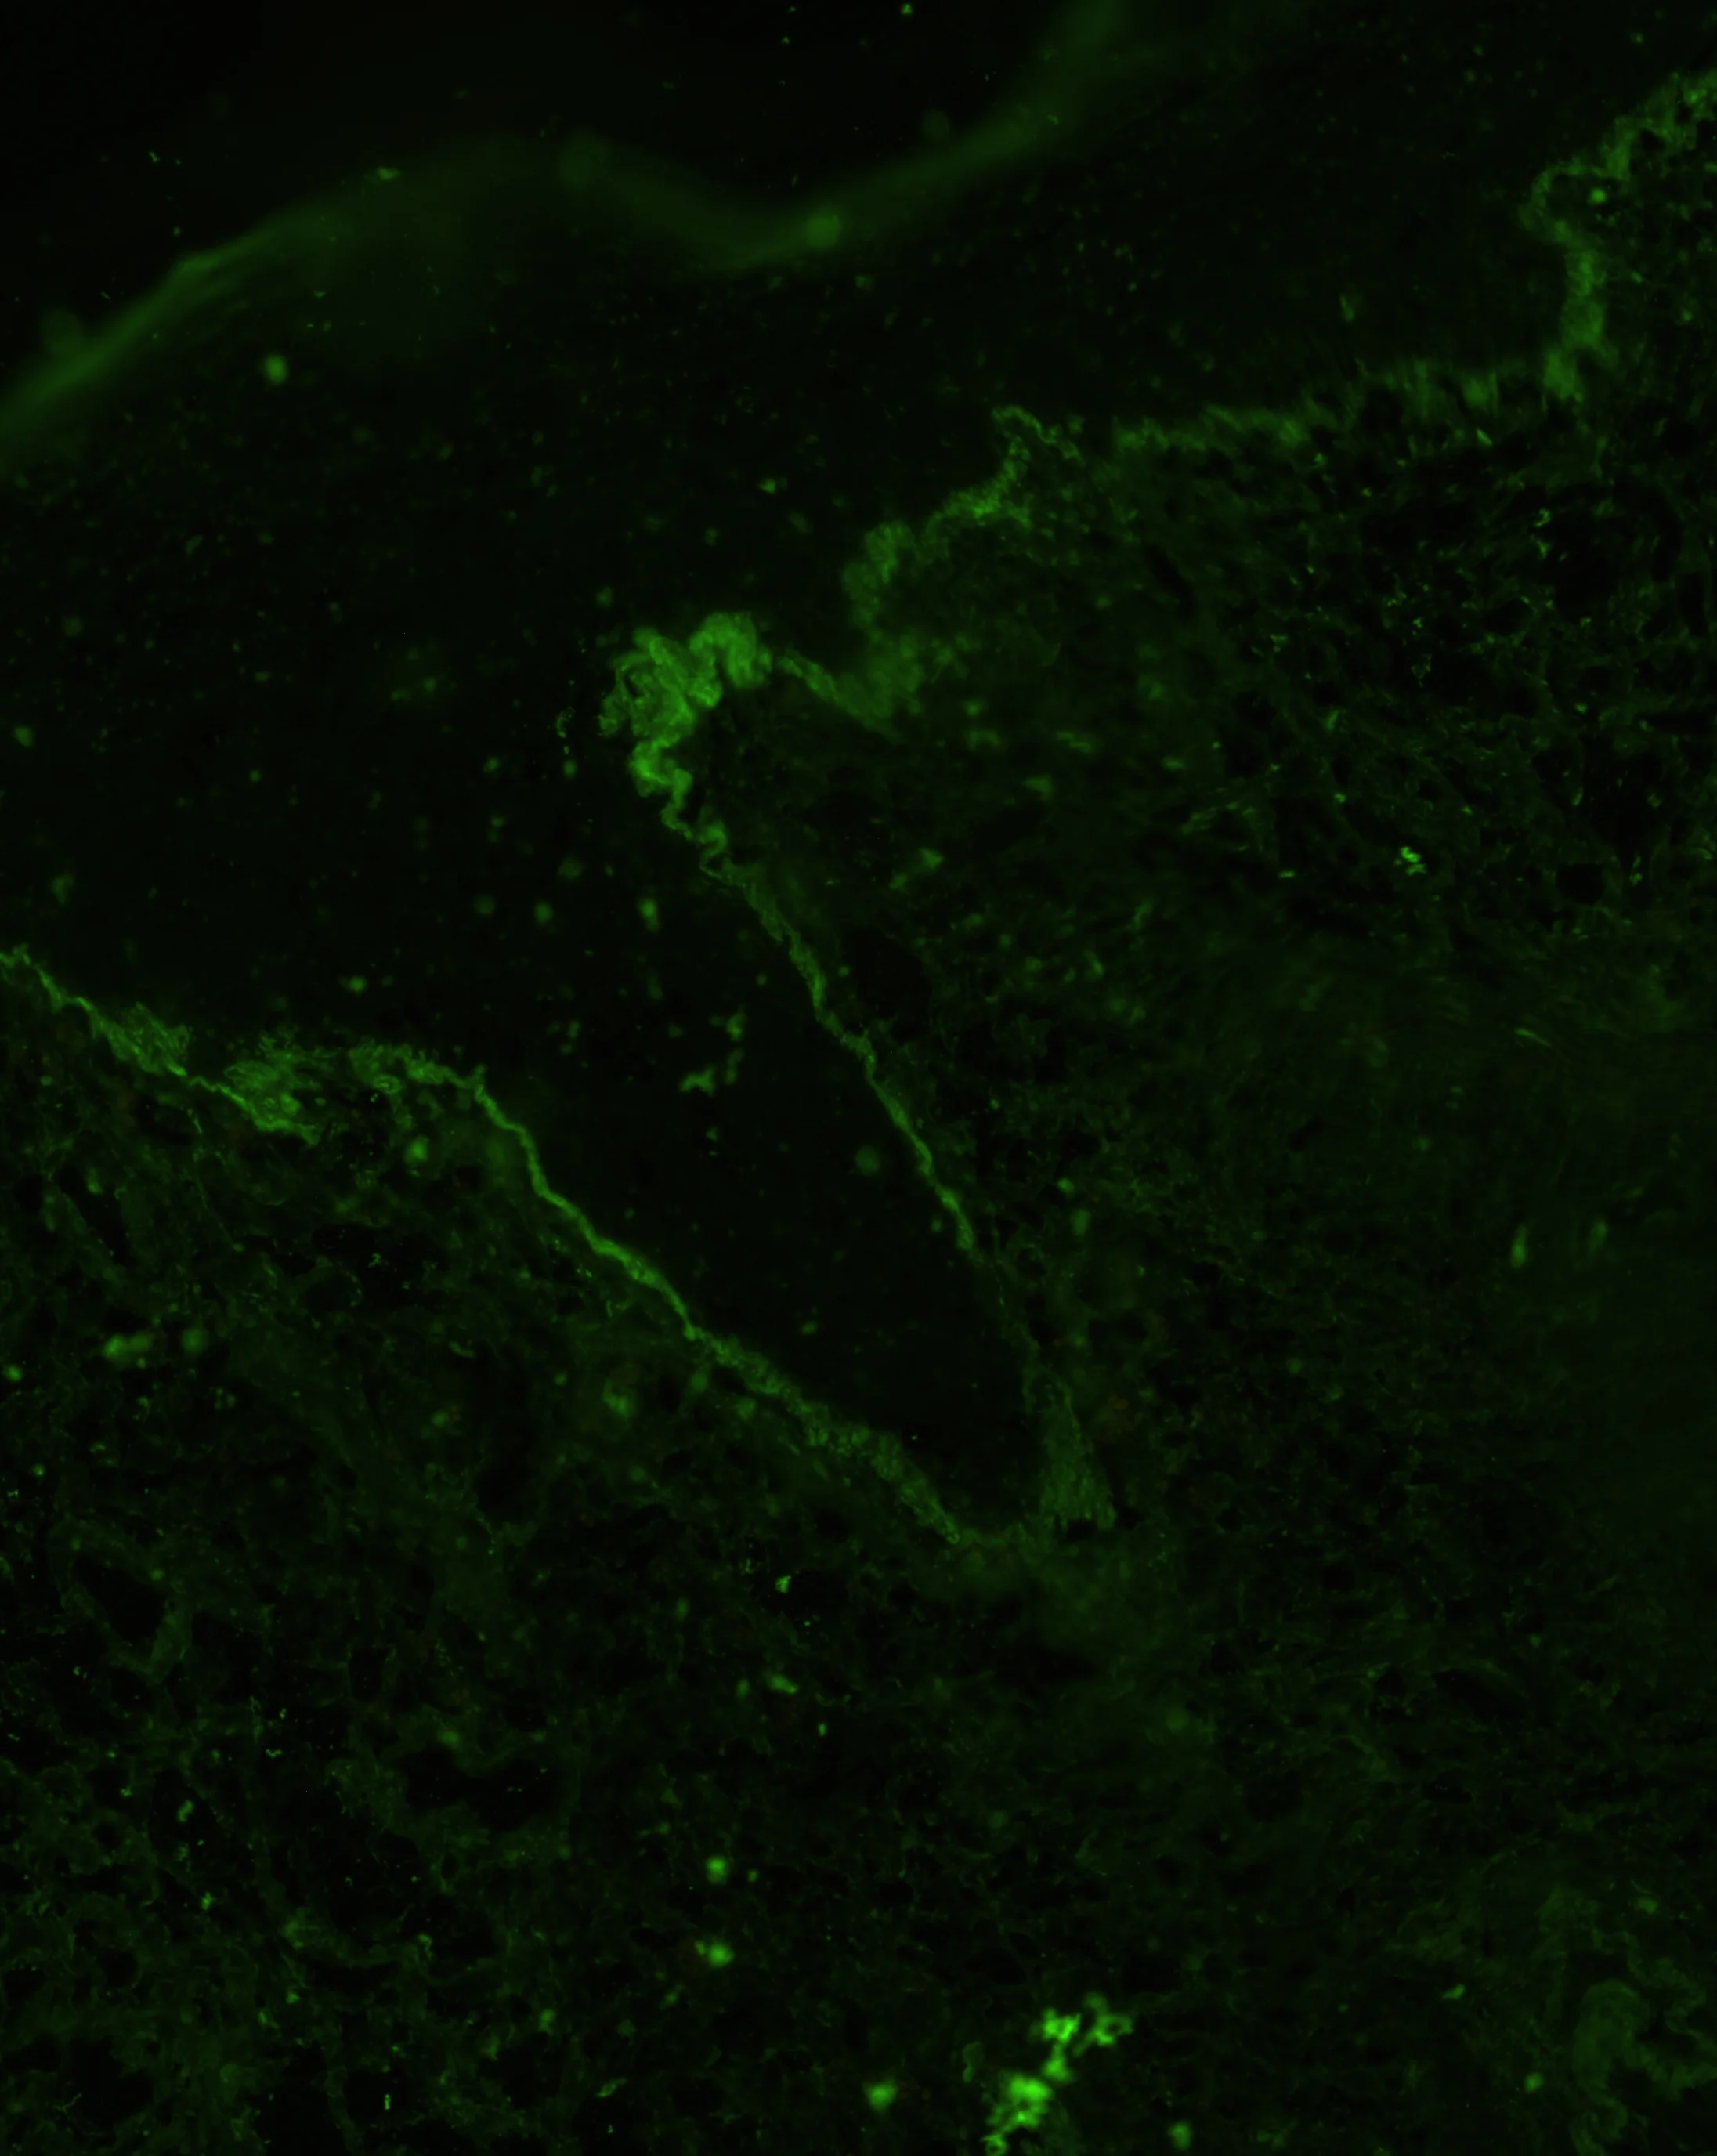

IgG

IgM

C3